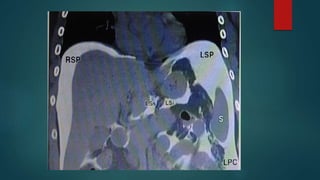

Left sided peritoneal spaces

Perihepatic spaces-

The anterior perihepatic

The posterior perihepatic

Left Subphrenic space

 LAS- diaphragm ant& lat,

stomach post.

 communicates with the post

subphrenic(perisplenic) space

 The perisplenic space surrounds

most of the spleen except for a

portion of spleen lying within the

splenorenal ligament

Left sided peritonealspaces Perihepatic spaces- The anterior perihepatic The posterior perihepatic

Left Subphrenic space LAS- diaphragm ant& lat, stomach post.  communicates with the post subphrenic(perisplenic) space  The perisplenic space surrounds most of the spleen except for a portion of spleen lying within the splenorenal ligament